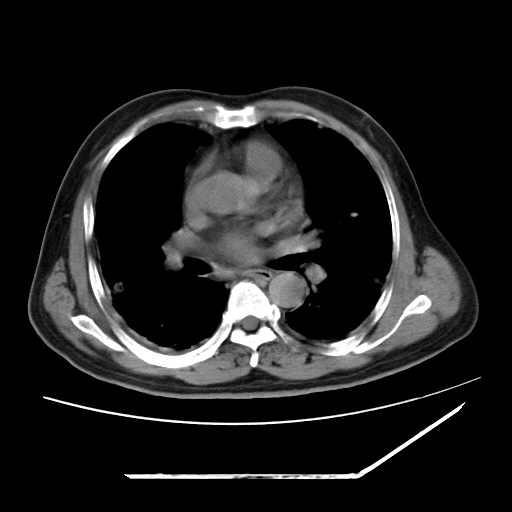

男,57,畏寒,发热

两肺野多发大小不一高密度灶,纵膈内见肿大淋巴结,要考虑转移瘤可能。双侧胸腔少量积液。

双肺多发结节样病灶,部分内见透光区,纵隔内见淋巴结肿大。结核临床如有畏寒,高热,白细胞增高首先考虑迁徙性肺脓肿(多是金黄色葡萄球菌感染)。

注意除外转移瘤。

1)考虑两肺感染性病变(金黄色葡萄球菌肺炎?);建议抗炎治疗后复查排除其他。2)双侧少量胸腔积液。